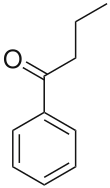

| Preferred IUPAC name

1-Phenylbutan-1-one | |||

| C10H12O | |||

Butyrophenone is an organic compound with the formula C6H5C(O)C3H7. It is a colorless liquid.

The butyrophenone structure—a ketone flanked by a phenyl ring and a butyl chain—forms the basis for many other chemicals containing various substituents. Some of these butyrophenones are used to treat various psychiatric disorders such as schizophrenia, as well as acting as antiemetics.[1]